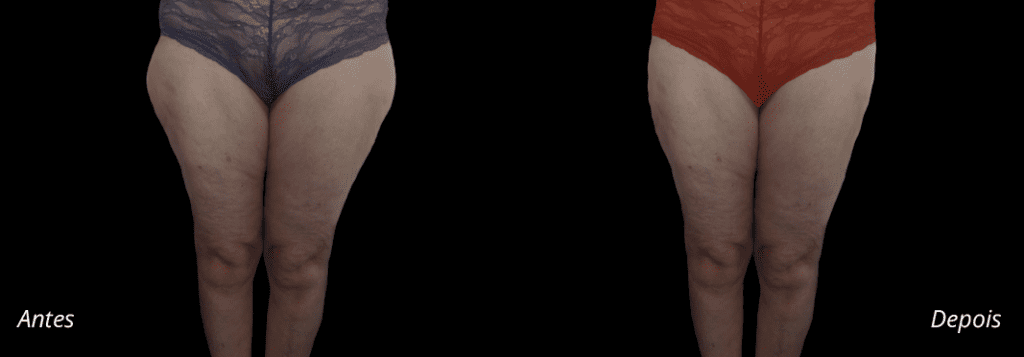

Imagens antes e depois